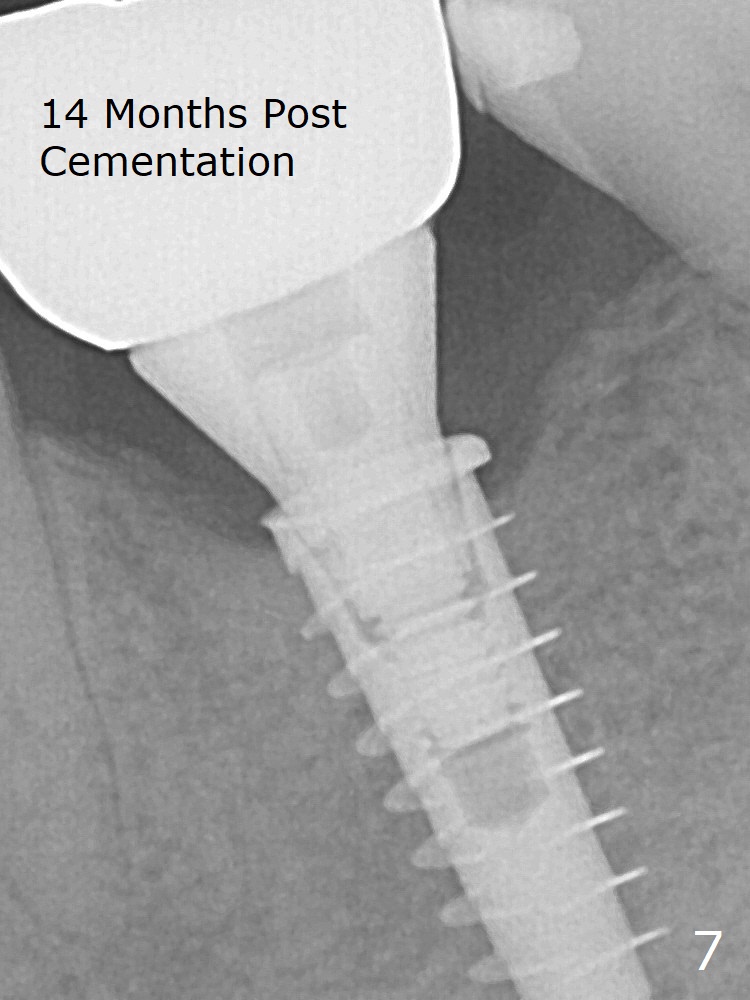

While the mesial ridge is relatively wide associated with residual root at #19 (Fig.1 <), the distal one is narrow (*). Osteotomy is initiated distal to the mesial socket (Fig.2,3 *). Due to the narrow ridge, a 4.5x11 mm implant is placed (Fig.4); before as well as after placement of a 6x4(3) mm abutment, the mesial socket (*) is filled with Vera graft and autogenous bone as well as collagen plug. Following suturing, periodontal dressing is applied to the wound. There is no apparent bone loss 7 months postop (Fig.5,6) or 14 months post cementation (Fig.7). In fact the abutment has been incompletely seated (Fig.5-8), which may be related to #13 failure. The ridge appears to be narrow for the 4.5 mm implant 1.5 years post cementation (Fig.9). When a lady looks skinny with sign of the narrow ridge, choose an implant as narrow as possible.